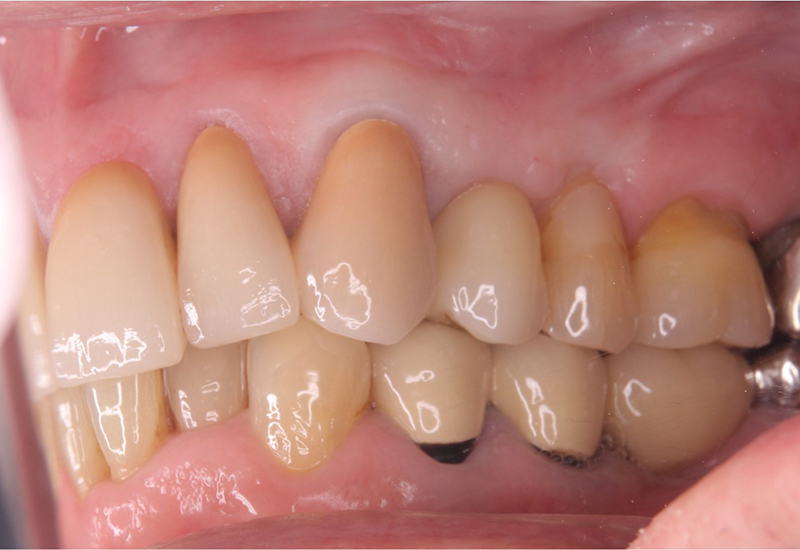

治療後 |